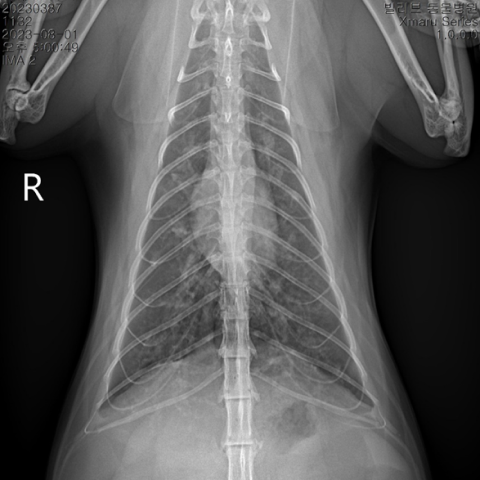

ºñ°­, ºÎºñµ¿, ÀÎ/ÈĵΠÂÊ¿¡ ¿°ÁõÀÌ »ý±â´Â »óºÎÈ£Èí±âÁúȯÀÇ °æ¿ì Àçä±â, Ä๰, °ÅÄ£ ¼û¼Ò¸®, °á¸·¿° µîÀÇ Áõ»óÀÌ ³ªÅ¸³¯ ¼ö ÀÖ°í, ±â°üÁö³ª Æó¿¡ ¿°ÁõÀÌ »ý±â´Â ÇϺÎÈ£Èí±âÁúȯÀÇ °æ¿ì È£Èí ÀÌ»ó, ±âħ µîÀÇ Áõ»óÀÌ ³ªÅ¸³¯ ¼ö ÀÖ½À´Ï´Ù.

°¡º­¿î Áõ»óÀÇ °æ¿ì Áõ»óÀ» ¿ÏÈ­ÇÒ ÀÖ´Â ¾à¹° Ä¡·á¸¦ ¿ì¼±Çϰí, Áõ»óÀÌ Àß ³´Áö ¾Ê°Å³ª ½É°¢ÇÒ °æ¿ì¿¡´Â ¿øÀÎ °¨º°À» À§ÇØ ¹æ»ç¼±, È£Èí±â PCR °Ë»ç, ±â°ü¼¼Ã´ °Ë»ç µîÀ» ÇØº¼ ¼ö ÀÖ½À´Ï´Ù.

ÀϹÝÀûÀ¸·Î ¾à¹°Ä¡·á¿Í ºÐ¹«(ÈíÀÔ)Ä¡·á¸¦ º´ÇàÇÏ°Ô µÇ¸ç, Áõ»óÀÌ ½ÉÇÏ¿© ½Ä¿åÀ̳ª ±â·Â ÀúÇÏ, ½Å°æ Áõ»ó µîÀÌ ³ªÅ¸³ª´Â °æ¿ì¿¡´Â ÀÔ¿ø Ä¡·á¸¦ ÇÕ´Ï´Ù.